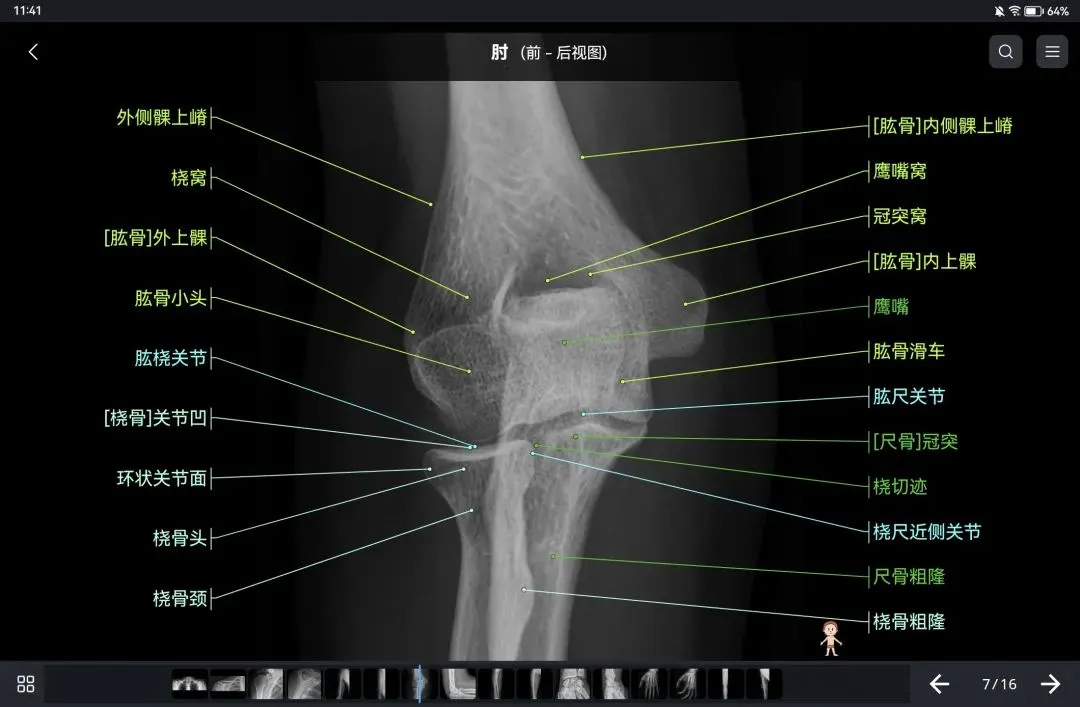

覆盖了X光、CT、MRI、断层大体解剖、核医学、介入造影、医学插图等多个模块,覆盖全身各个系统的影像解剖(正常解剖结构,无病例),其中的解剖结构高达87万个,结构标注超精细,超高清图像,历时两年研发设计完成✅。